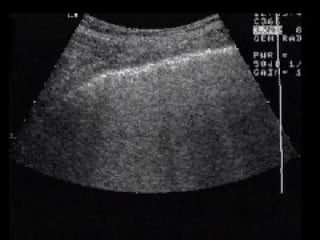

PROCEDURE Approach #2 –Anterior -Mid-Axillary View

PROCEDURE Landmarks Aproach #2 –Anterior Mid-Axillary View 1 Place probe longitudinally in right anterior mid-axillary line with marker towards the head 2 Look for IVC running longitudinally adjacent to liver crossing the diaphragm. 3 Track superiorly until it enters right atrium confirming that it is the IVC and not the aorta.